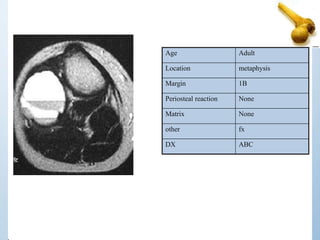

Age Adult

Location metaphysis

Margin 1B

Periosteal reaction None

Matrix None

other fx

DX ABC